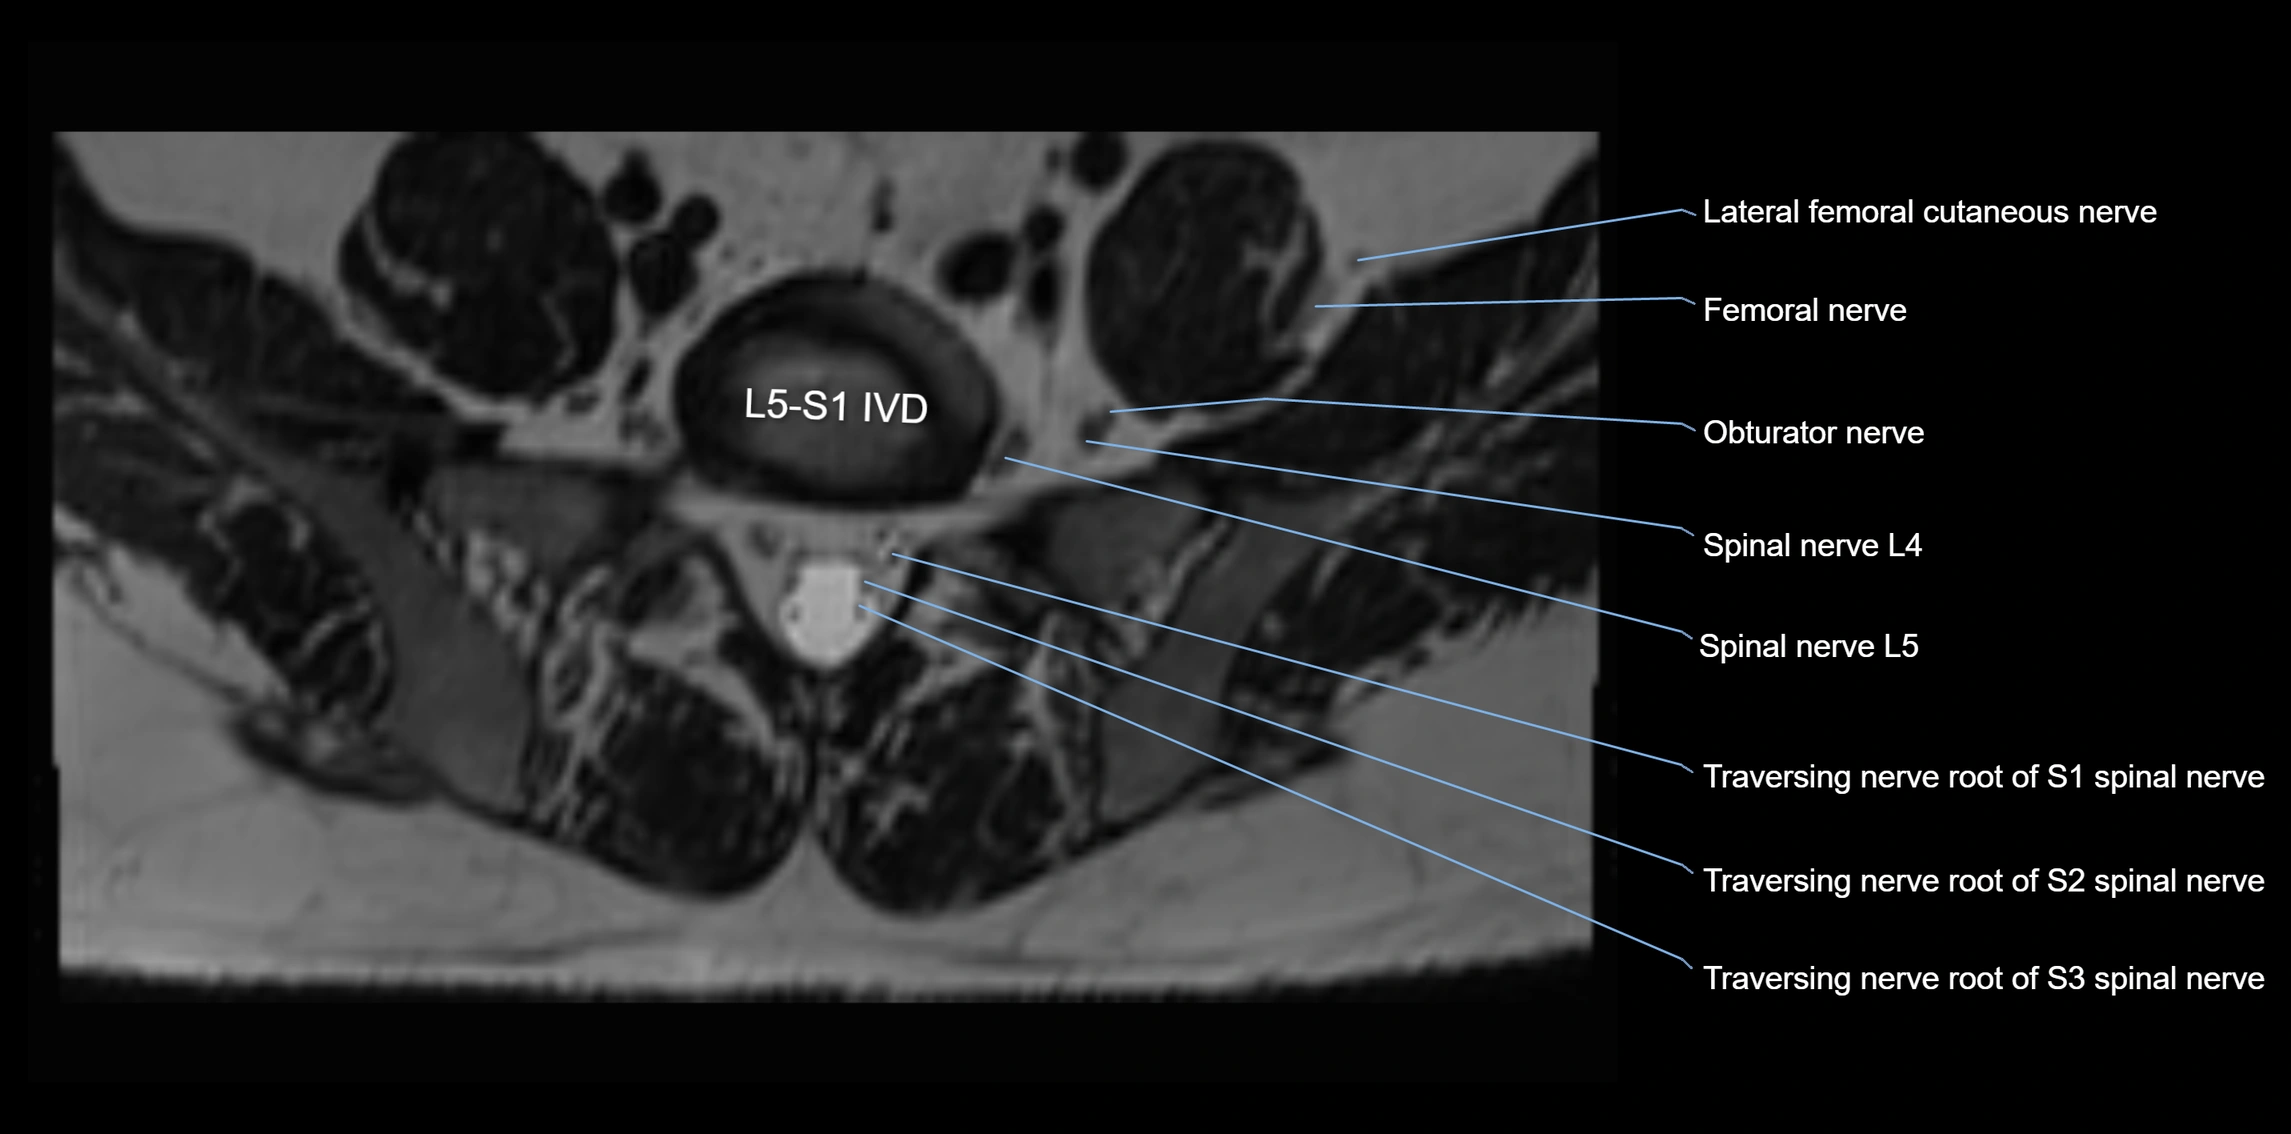

MRI image

image